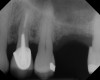

The implant is then delivered and should be well stabilized in the bone. If there is any mobility of the implant, it can either be placed a little deeper (if there is enough native bone) or the implant can be removed and the procedure aborted, in which case it would be a two-stage procedure. This should rarely occur with the tapered designed implant, even with only 2 mm of native bone. Using a bone-level platform-shifting implant (or a tissue-level designed implant) is critical, as the hard and soft tissue will establish a biologic width. If an external hex type of implant is used and the shoulder is placed at the bone level, an expected bone loss of 1.5 mm to 2 mm will occur.24 Figure 10 shows proper bone-level implant depth placement with a platform-shifting design. In this case, a 3-mm healing abutment was placed at the time of surgery to avoid a secondary uncovering surgery, but an implant-level healing abutment could have been placed instead. As can be seen, there was only about 2 mm to 3 mm of native bone height. The membrane was raised about 8 mm to 9 mm. Comparing the radiograph on the day of surgery (Figure 10) to the 6-month postoperative radiograph (Figure 11) shows no loss of native bone, as well as the positive change in appearance of the grafted bone. The 3.5-month CBCT scan (Figure 12) shows good healing of the bone with no coronal bone loss. With minimal native bone present, as in this case, the use of a non-platform-shifting or non-tissue-level implant design could be problematic. After 1.5 mm to 2 mm of crestal bone loss, an external hex designed implant could develop instability with possible implant failure. If a non-tapered implant is used and bone loss occurs during healing, migration of the implant into the sinus could potentially occur. The surgeon can use either a healing abutment or implant-level closure screw over the implant shoulder. With patients who tend to use their tongues to explore or play with the area, or if the area is under a removable partial denture, a closure screw is recommended.